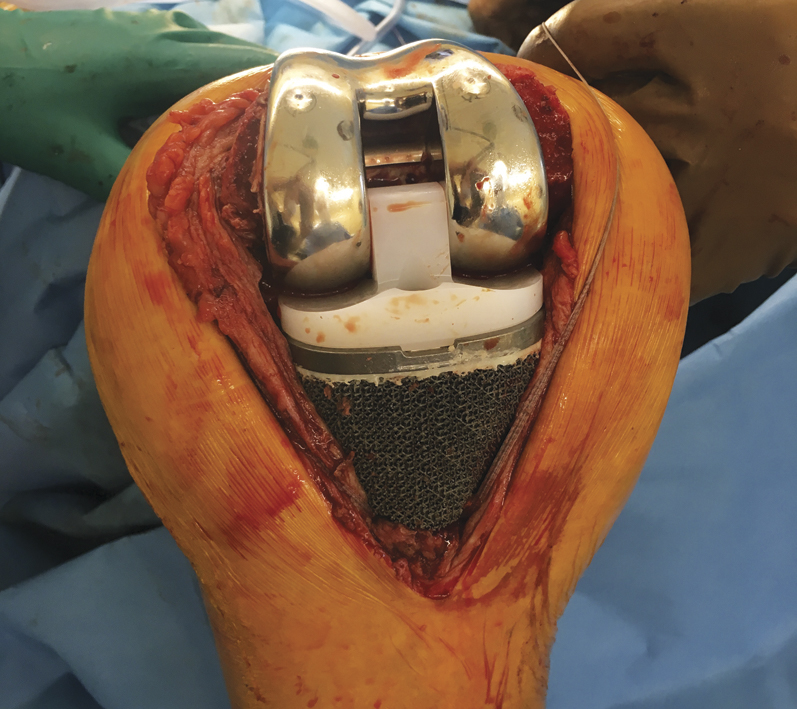

Оперативное вмешательство выполнялось под спинальной анестезией в положении пациентки лежа на спине. Из переднего доступа по старому послеоперационному рубцу была выполнена артротомия правого коленного сустава, выделилось около 20 мл желтоватой синовиальной жидкости, которая была взята для микробиологического исследования. Также произведен забор фрагментов тканей из пяти различных участков для исследования в бактериологической лаборатории. Затем были удалены компоненты цементного спейсера. В связи с тем, что мягкие ткани коленного сустава имели выраженные рубцовые изменения, с трудом был выполнен доступ к суставным концам бедренной и большеберцовой костей. Из доступных отделов удалена синовиальная оболочка, осуществлены краевая моделирующая резекция и денервация надколенника. Проксимальный отдел большеберцовой кости практически отсутствовал до диафиза на протяжении 6–7 см от верхушки головки малоберцовой кости, что делало его неопороспособным для установки стандартного варианта ревизионного эндопротеза (рис. 4).

Рис. 4. Массивный костный дефект типа 3 по классификации AORI

Дефект кости замещен индивидуальным имплантатом, изготовленным по 3D-технологии. С использованием стандартного набора инструментов смоделированы костные ложа для компонентов полусвязанного эндопротеза: размер бедренного компонента — Е, большеберцового — 4. Для сохранения ротации бедренного компонента использованы задние аугменты 5 мм.

Для диафизарной фиксации бедренного компонента смоделирован костномозговой канал бедренной кости под прямую интрамедуллярную ножку диаметром 16 мм, длиной 100 мм. Дефект проксимального отдела большеберцовой кости замещен индивидуальным имплантатом, изготовленным посредством прототипирования, большеберцовая ножка — прямая, диаметром 14 мм, длиной 100 мм. Место прикрепления связки надколенника на большеберцовой кости отсутствовало, что потребовало фиксации рубцово-измененной связки надколенника с использованием двух синтетических лент шириной 2 мм к аугменту. Осуществлена пробная сборка компонентов эндопротеза с вкладышем 10 мм — сустав стабилен. Имплантированы оригинальные компоненты. Для профилактики развития инфекционного осложнения использованы две дозы костного цемента с добавлением терморезистентных антибиотиков. Сустав стабилен, амплитуда движений 0/0/70°. Наложен послойный шов раны (рис. 5).

Рис. 5. Установлены окончательные компоненты полусвязанного эндопротеза с индивидуальным имплантатом, замещающим дефект большеберцовой кости